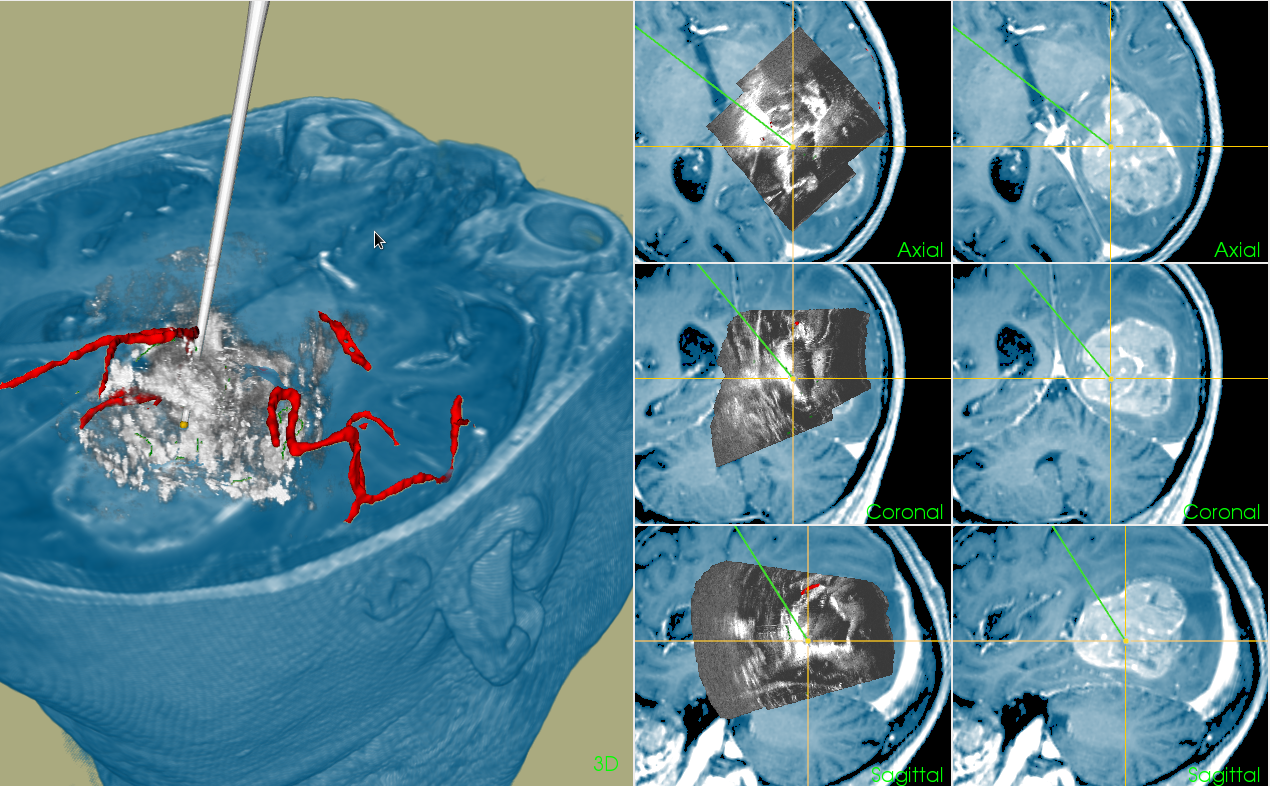

En nasjonal navigasjonsplattform for bildeveiledet terapi for forskere ved alle norske universitetsykehus.

En del av NorMIT er å bygge og vedlikeholde en navigasjonsplattform som skal gjøres tilgjengelig for forskere ved alle norske universitetsykehus. Plattformene baseres på eksisterende arbeid hos Intervensjonssenteret, samt CustusX som er utviklet av SINTEF. Utviklingen gjøres ved SINTEFs Avdeling for medisinsk teknologi i samarbeid med Nasjonal kompetansetjeneste for ultralyd og bildeveiledet behandling.